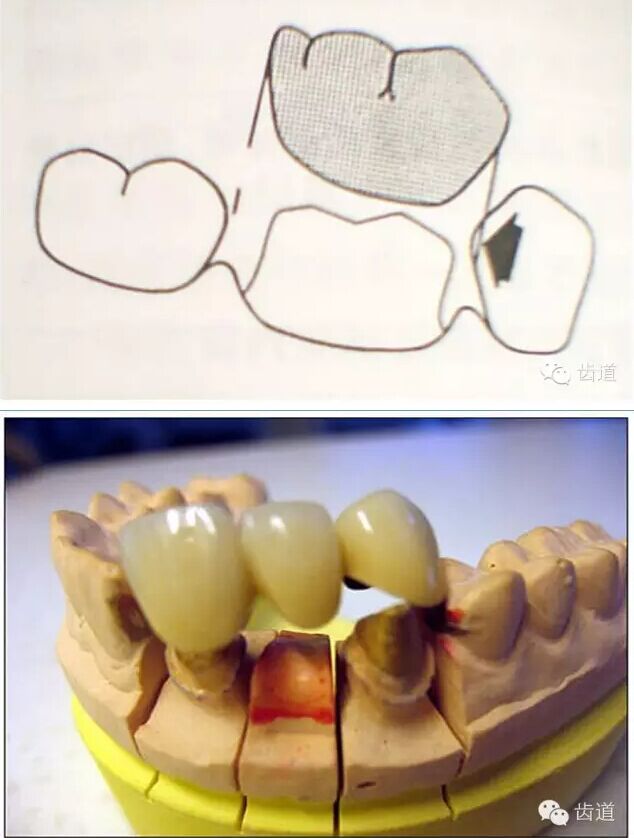

l實際備牙產(chǎn)生的問題